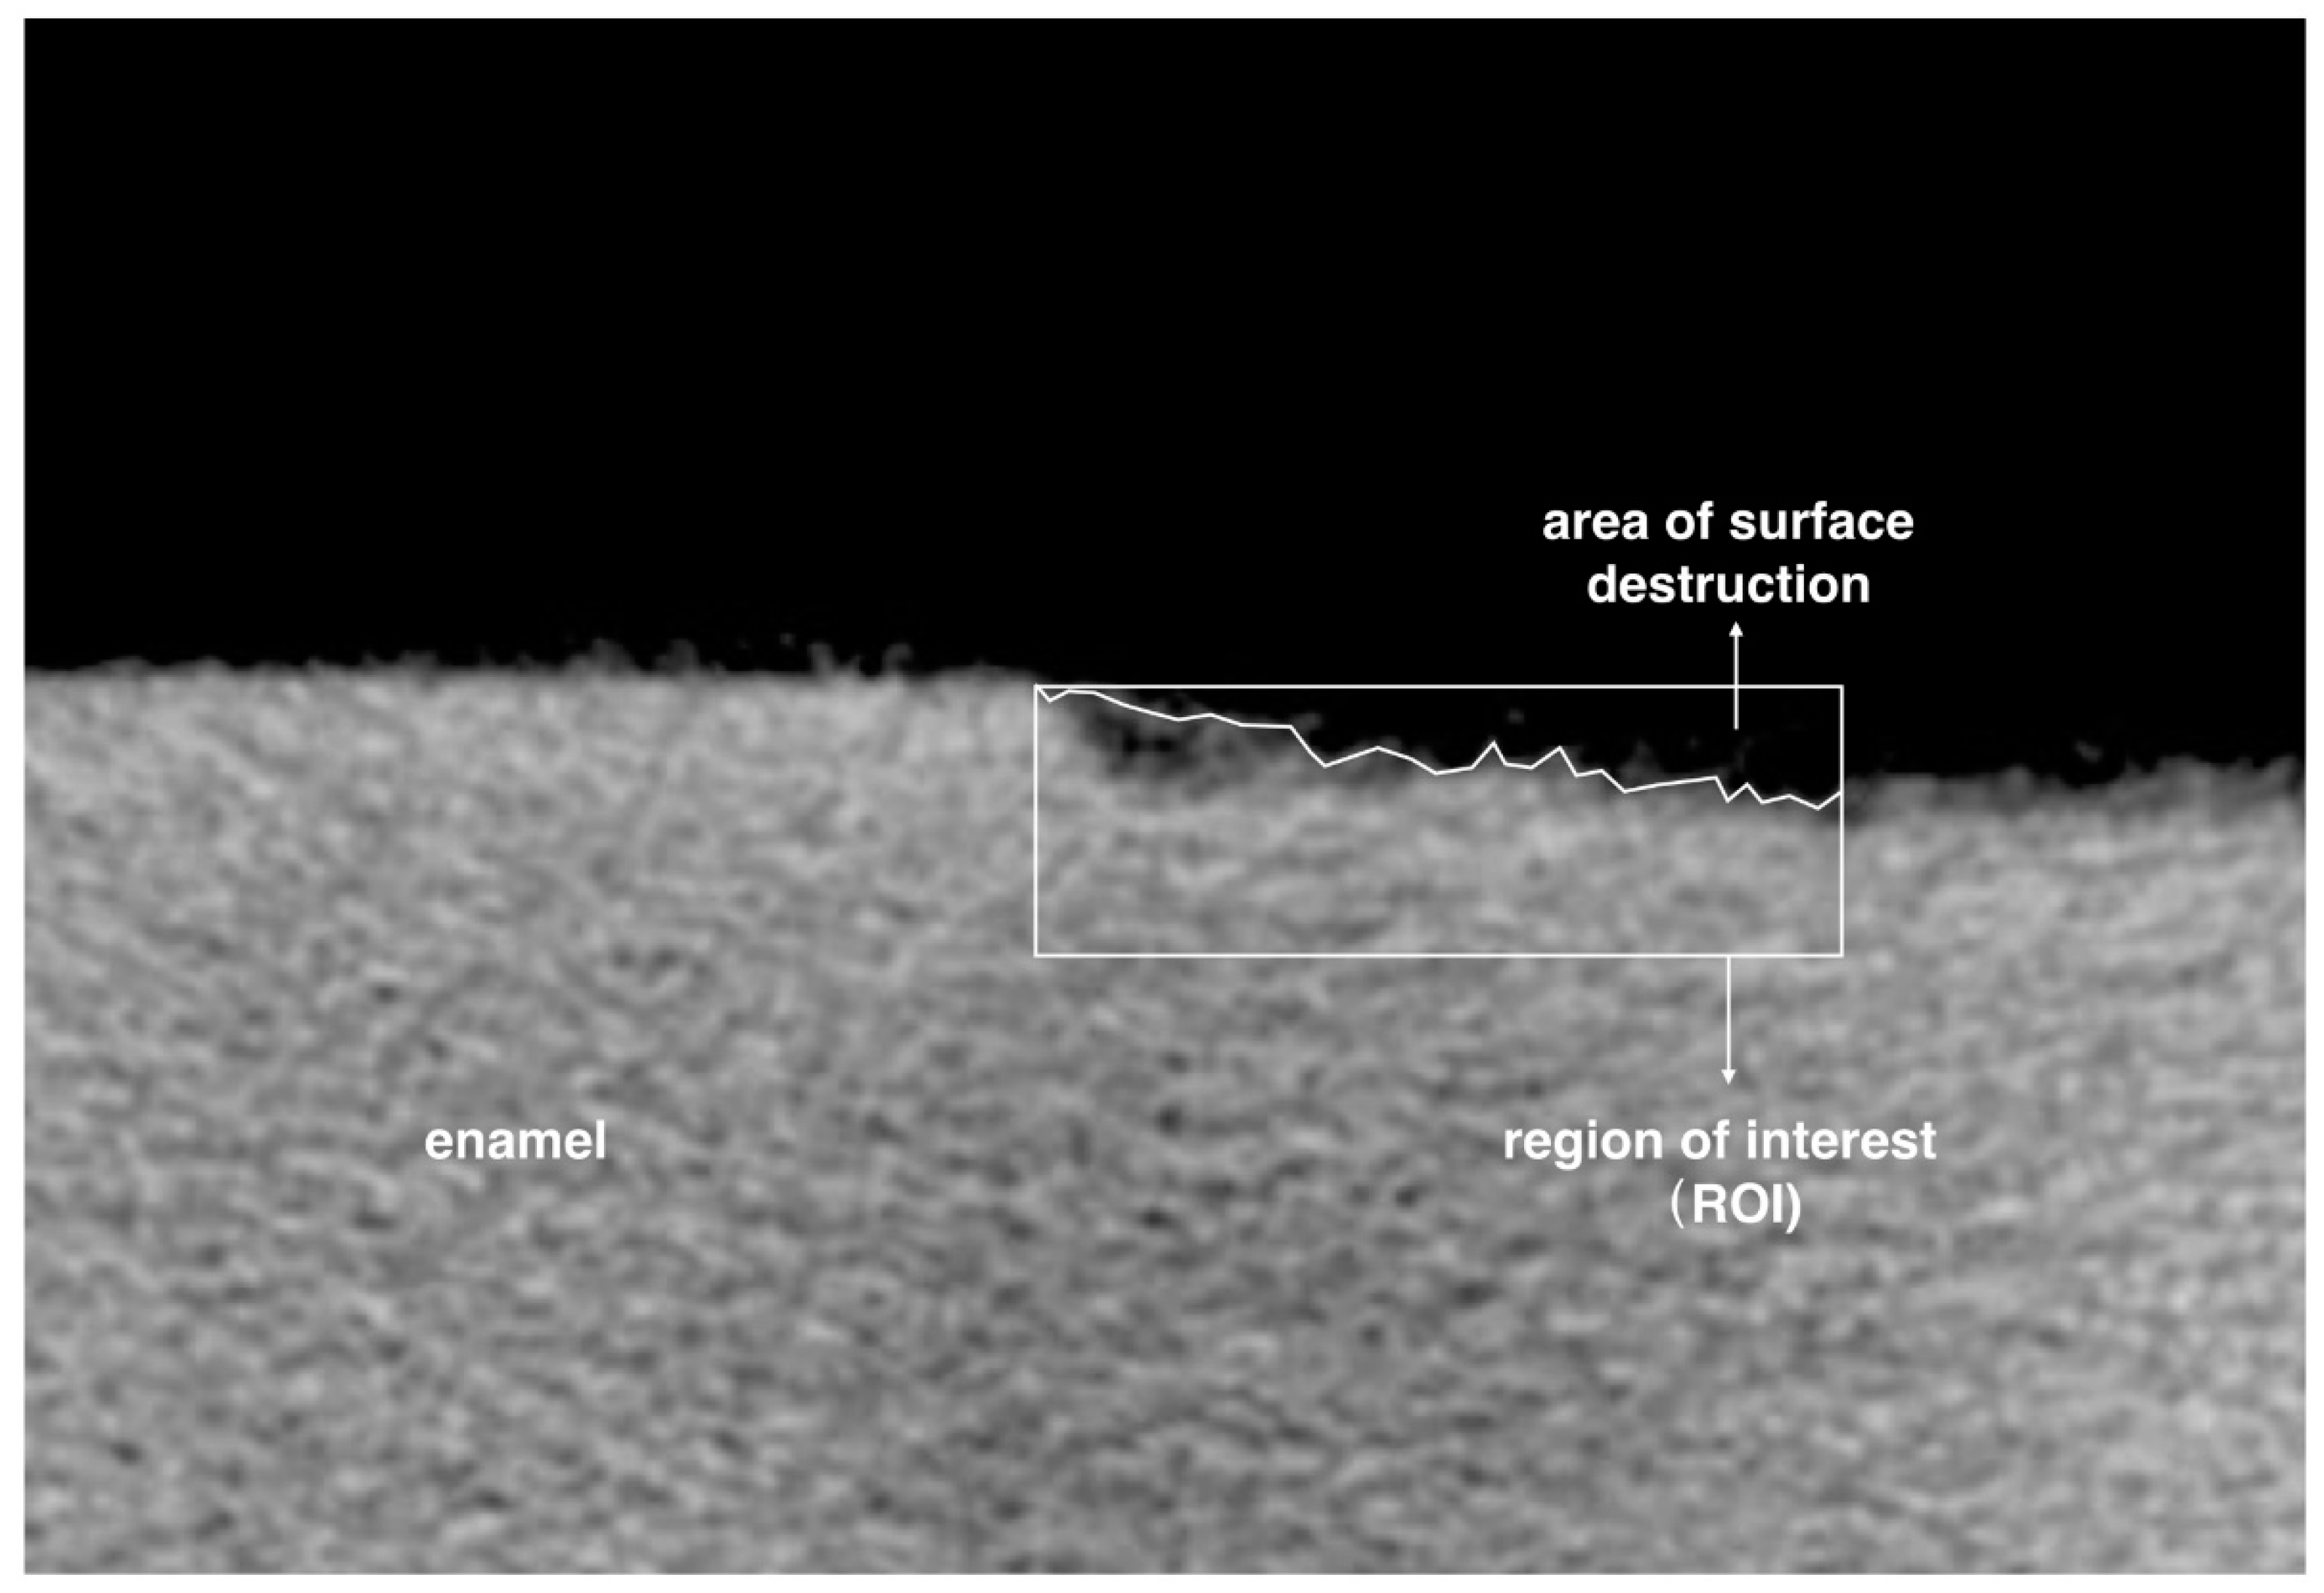

4.2.1. Lesion Depth, Mineral Loss and Surface Destruction

| ROI | region of interest |

| Surface destruction (%) | 7.8 ± 8.93 a | 0.71 ± 1.6 b | 0.36 ± 1.70 b | 1.36 ± 2.94 b | <0.001 a > b |